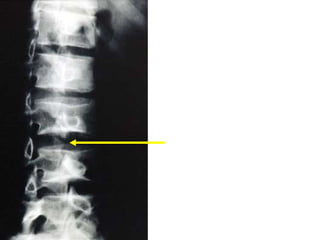

椎弓解離症 spondylolysis